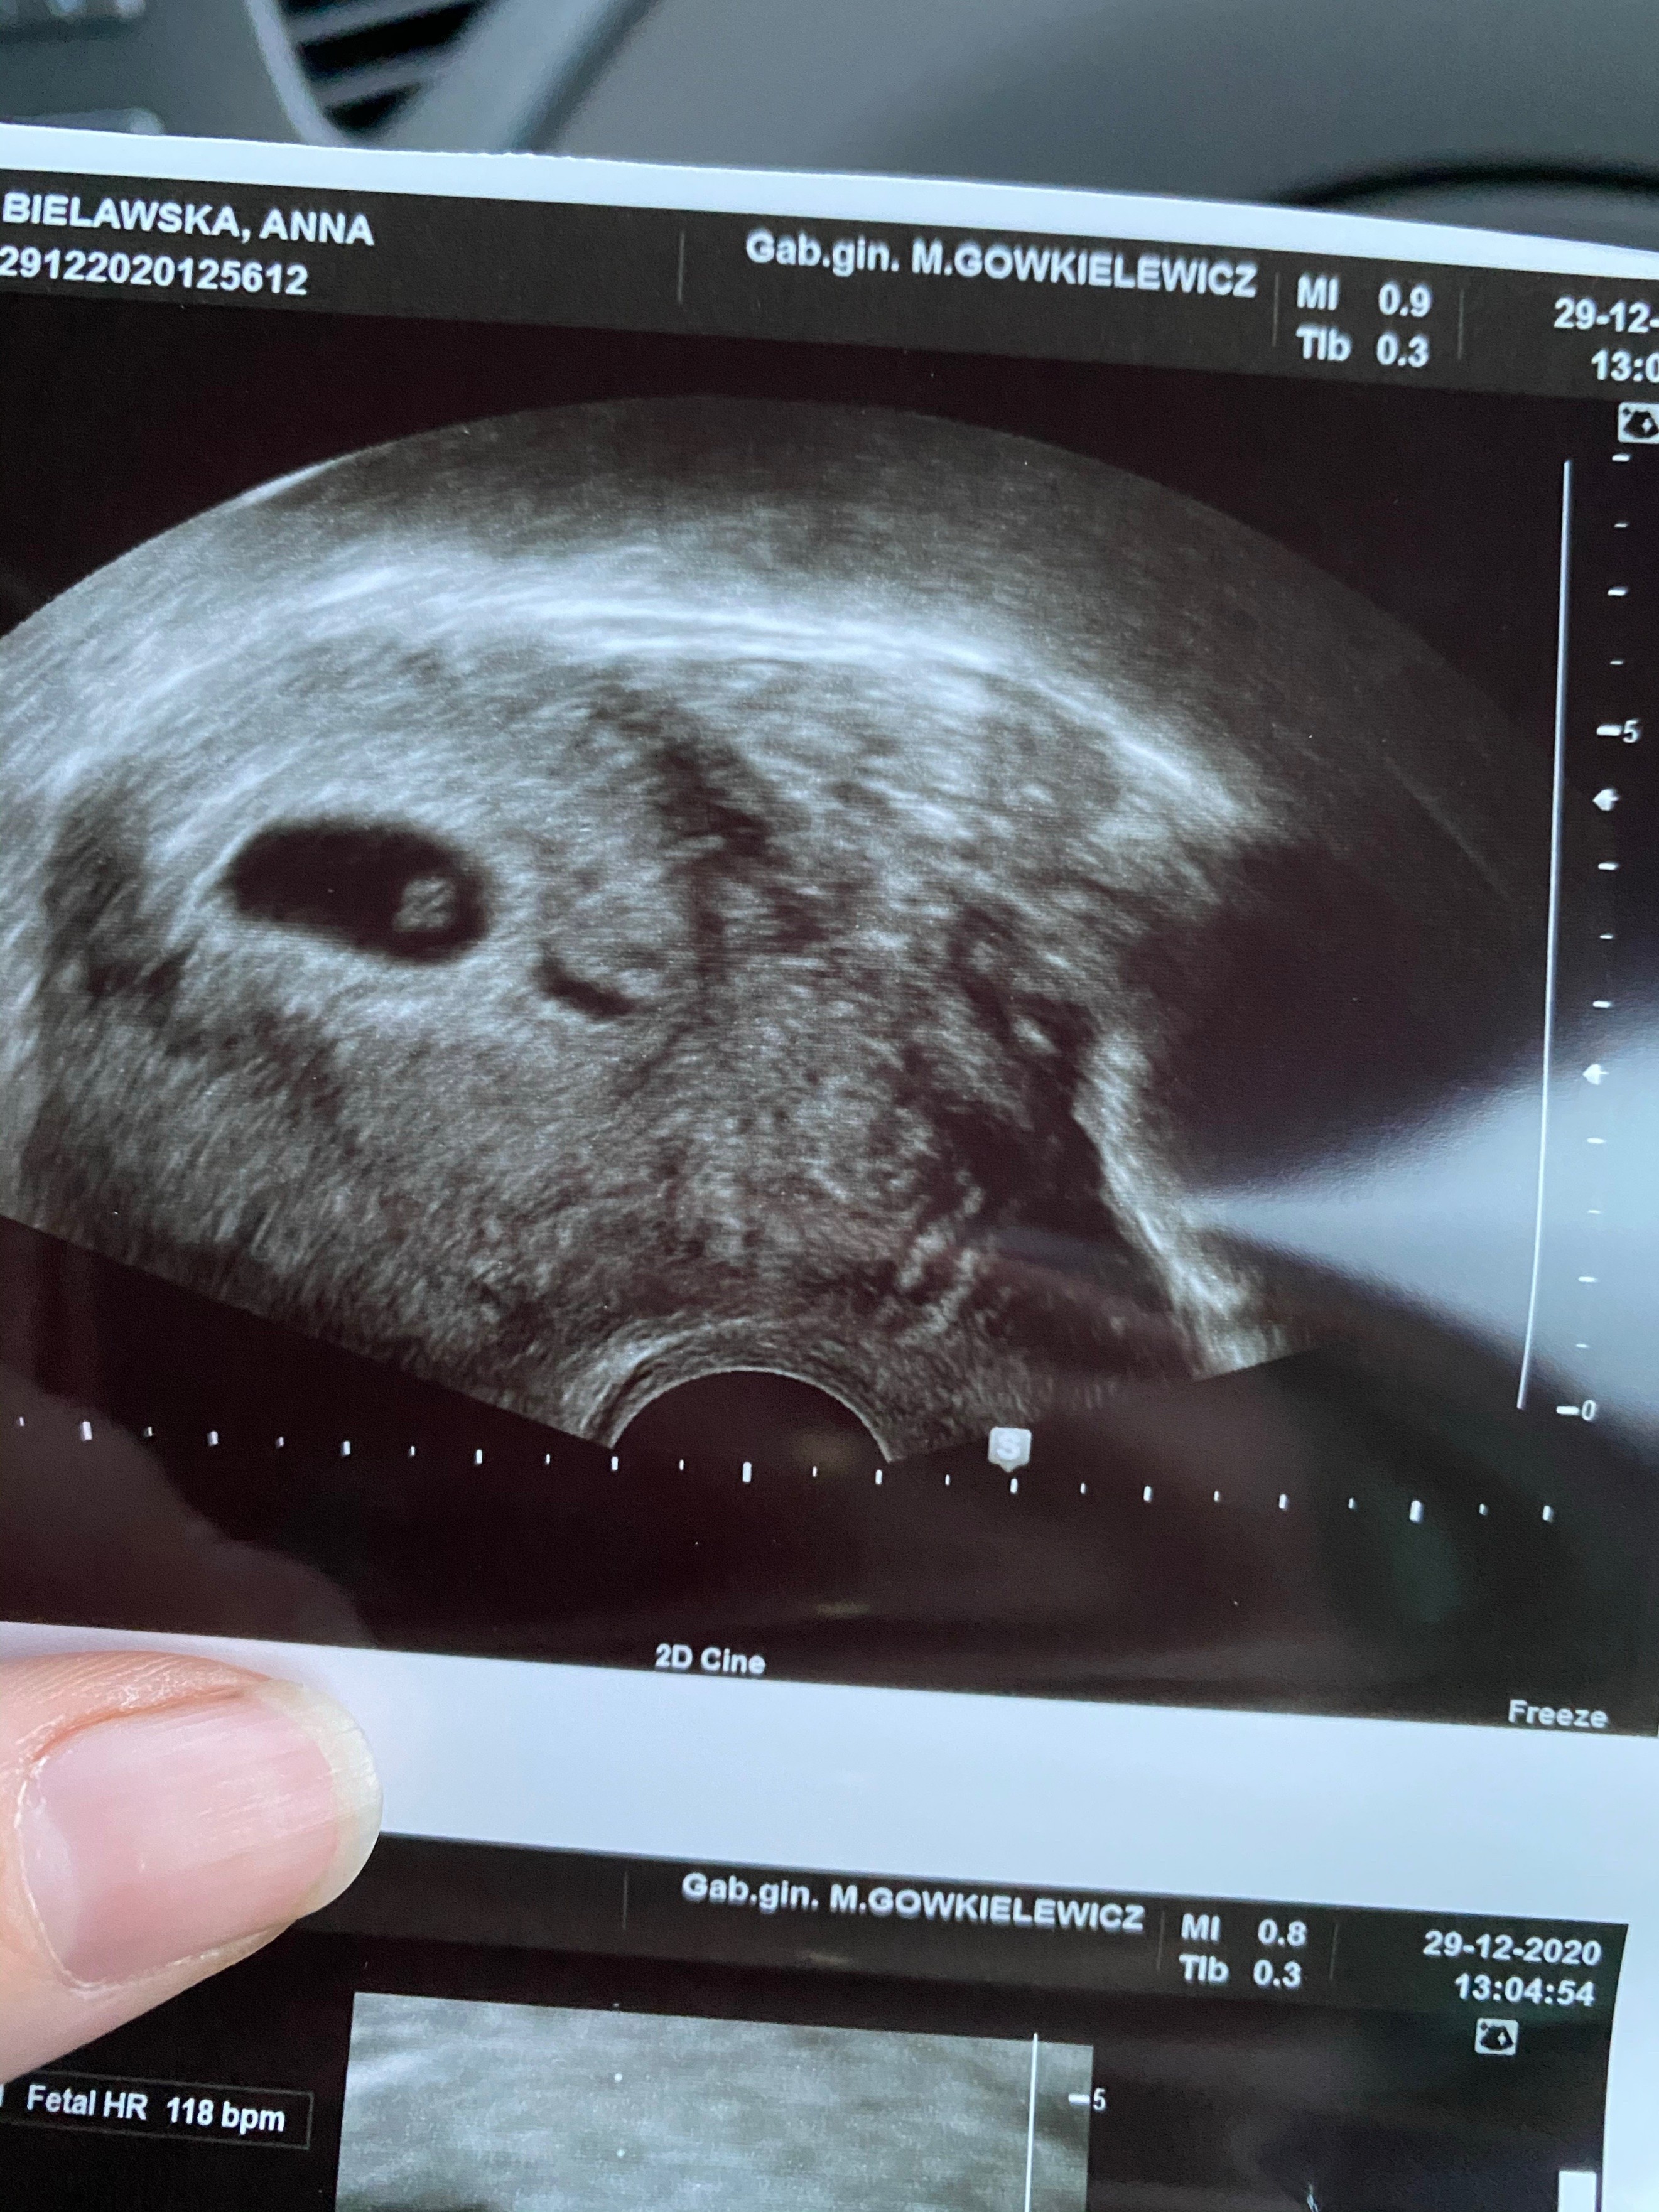

Wszystko dobrze. Maluszek tydzien młodszy ale serduszko pieknie bije. Widzialam jak caly pulsowal.

Termin z usg to 24.08. Odetchnelam z ulga. Zobacz załącznik 1220518